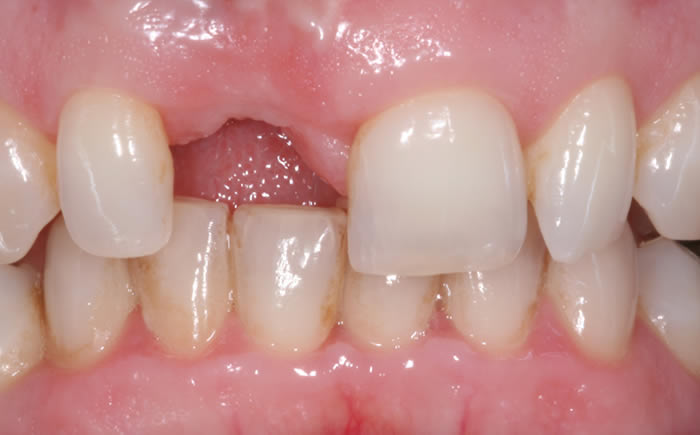

Before & After Gallery

More front teeth replaced by dental implants

Case Three (4 images)